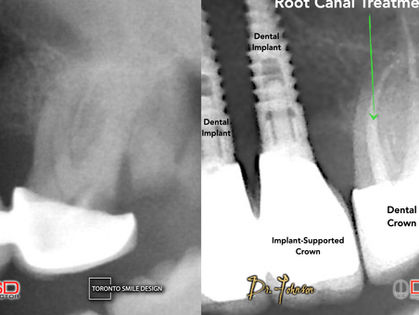

Root Canal

Root Canal: Ultimate Solution for Tooth Pain

A root canal is a dental treatment that cleans, disinfects, repairs, and saves damaged or infected teeth. Toronto dentist, endodontist saves